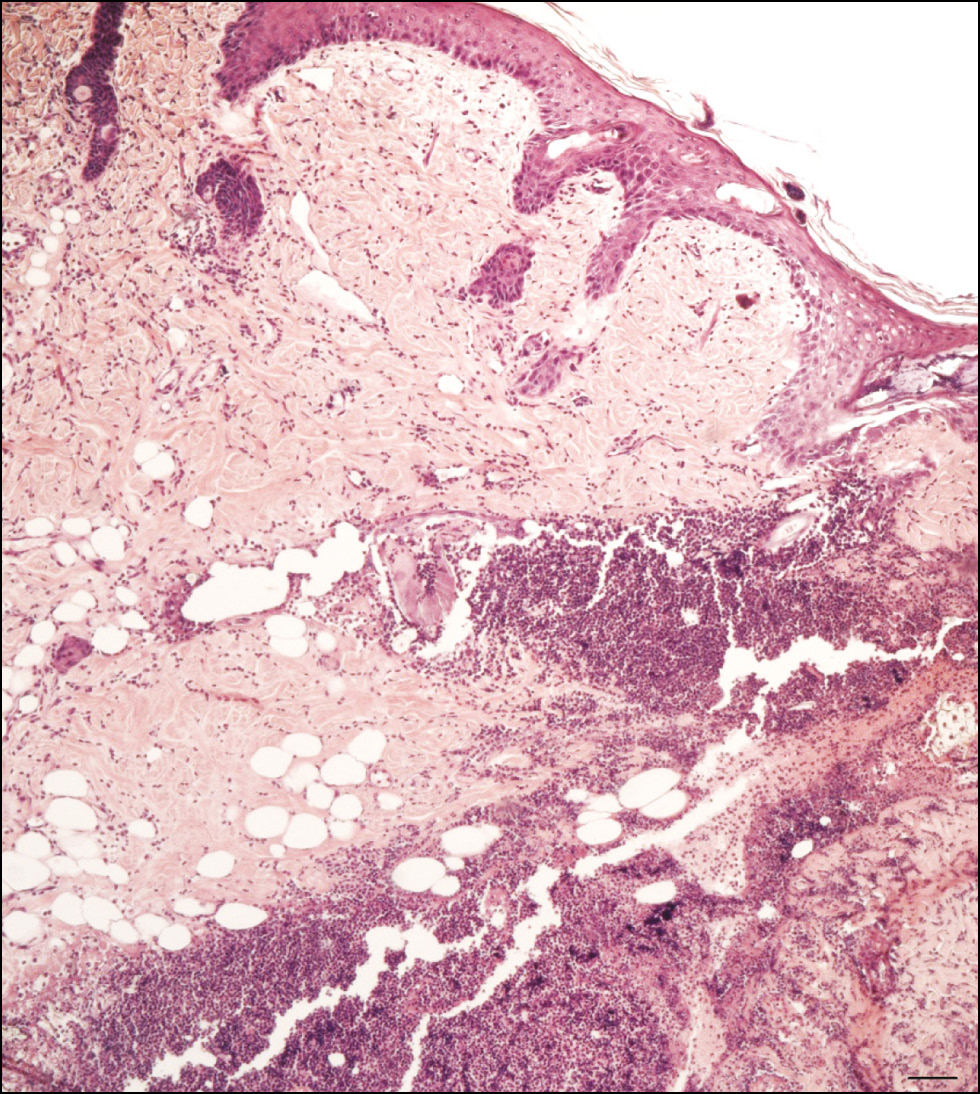

BACKGROUND: The proliferation to apoptosis ratio at a wound site is crucial for healing. Regenerative histogenesis of the skin in the perinecrotic zone is of key interest, specifically the connective tissue layers (the dermis and hypodermis). This zone is characterized by cambial elements of epithelial and connective tissues that drive regeneration, as well as distinctive cell death processes. Immunohistochemical methods are typically used to investigate patterns of histogenetic processes, including proliferation and cell death, in tissues with varying regenerative potential. However, selecting markers that reflect the proliferation to apoptosis ratio at different stages of regeneration remains challenging.

METHODS: An experimental single-center, continuous, controlled, randomized, non-blind study was conducted. Skin samples of the thigh from Wistar rats were obtained at various stages of healing after mechanical injury (deep incised wound). Animals were divided into nine groups: a control group of intact rats (n = 3) and eight experimental groups corresponding to post-injury time points of 12 hours, 24 hours, 2 days, 3 days, 6 days, 10 days, 15 days, and 25 days (n = 3 per group). Tissue fragments were processed for histological and immunohistochemical examination. Antibodies to phosphorylated histone H3 were used to assess proliferation, whereas apoptosis was detected using antibodies to p53 and caspase-3.

RESULTS: Immunopositive cells expressing phosphorylated histone H3, caspase-3, and p53 were identified in cutaneous connective tissue samples in all experimental groups. The proliferation index was determined, and changes in pro-apoptotic protein expression were analyzed in intact skin and the perinecrotic zone at different stages of regeneration. Based on these data, the proliferation to apoptosis ratio and an index characterizing both processes were calculated. The proliferation to apoptosis ratio was highest when proliferation prevailed over cell death (in intact skin and at the final stages of regeneration) and lowest when apoptosis predominated (inflammation and necrosis phases).